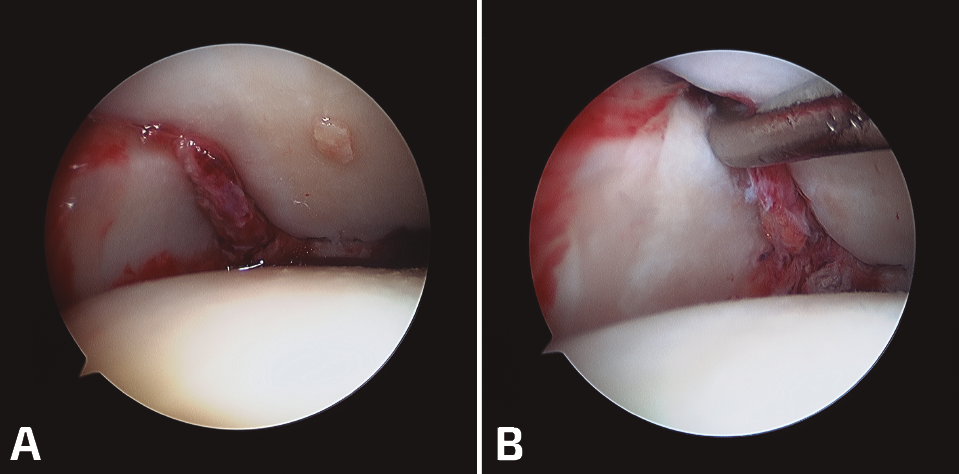

En las lesiones agudas de la sindesmosis sin fractura, lo que hallamos más frecuentemente es la interposición de partes blandas en el receso medial, que corresponde a la rotura o restos fibróticos de las estructuras ligamentosas del complejo medial. Es fundamental su desbridamiento para confirmar la reducción (Figura 3).

Figura 3. A: reducción correcta del peroné en su fosita tibial; B: palpamos la inestabilidad.